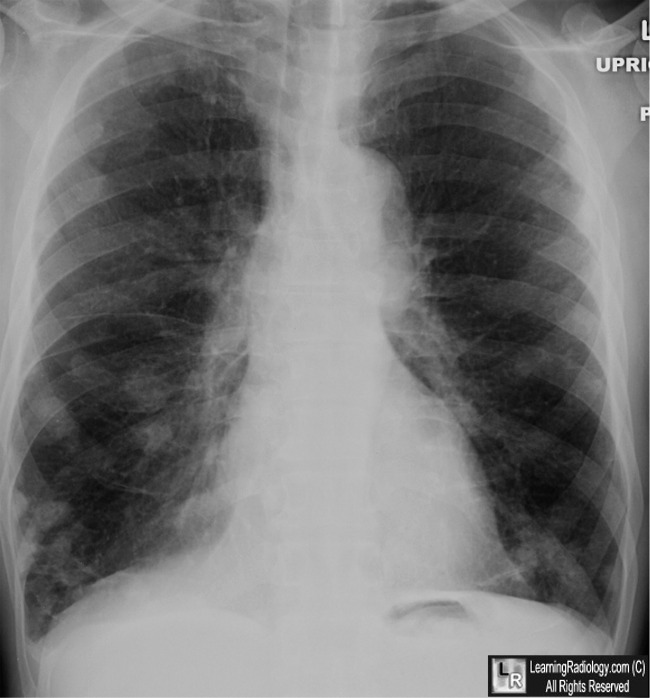

PULMONARY MANIFESTATIONS OF RHEUMATOID ARTHRITIS 669 Figure 1. A 71-year-old white man with rheumatoid arthritis (RA) and no pulmonary complaints. ... Get Content Here

RECURRENT PNEUMOTHORAX IN RHEUMATOID ARTHRITIS A. C. Robinson, J. Power, L. Clancy and E. Sweeney Department of Respiratory Medicine and Pathology, St. James's Fig. 1--Chest Radiograph showing resolution of pneumothorax. 437 . 438 Robinson et al. hJ.M.S. December, 1984 ... View Full Source

298 R.B. Levine and K.L. Sullivan: Rheumatoid Arthritis Fig. 1. A Portable chest examination of this 53-year-old woman demonstrates typical fmdings of rheumatoid arthritis, with superior ... Return Document